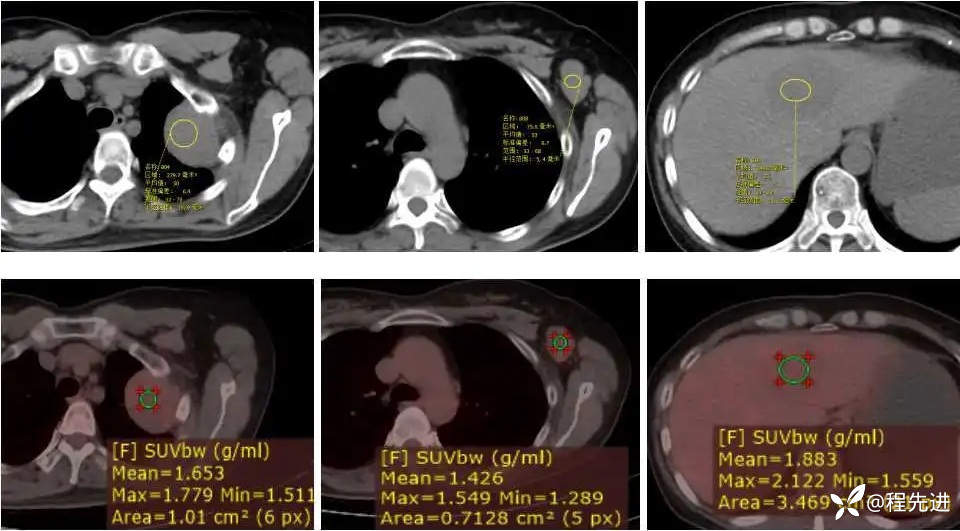

【主诉】:发现左胸部软组织肿块伴左侧腋窝淋巴结肿大1周

【现病史及既往史】:患者1周前因体检发现左肺上叶软组织肿块伴左侧腋窝淋巴结肿大。病程中患者无咳嗽咳痰,无胸闷胸痛,无发热、头痛、头昏、腹胀等不适精神及食纳尚可,二便正常